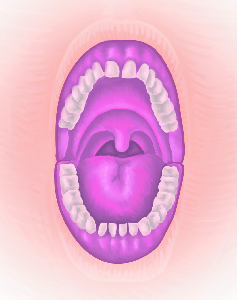

Detailreiche Fotografien aus der medizinischen Praxis ergänzen die Texte; moderne, genaue,

wissenschaftliche Zeichnungen geben Einblick in die Anatomie und die Funktion der Lunge und

anderer Organe.